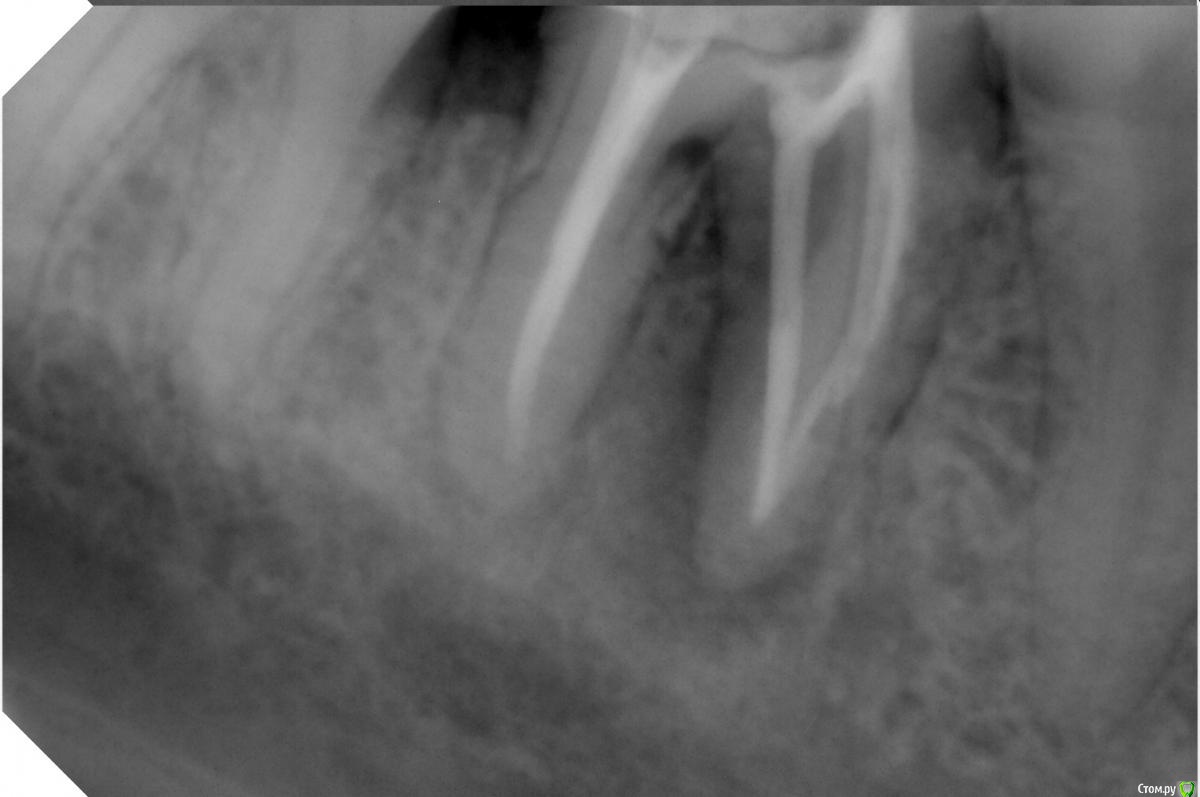

bogdan_r Опубликовано 23 июня, 2018 Поделиться Опубликовано 23 июня, 2018 Здравствуйте, у пациента жалобы на свищ, который не проходит уже 4 месяца(на момент обращения 3 месяца). Зондирование в норме. Перелечил каналы. Оставлял кальций 2 раза. Решил, что может, не достаточно плотно запломбировал и решил запломбировать гутаперчей. Вижу, что можно было сделать лучше, но свищ все равно остался. ММ канал искал, но не нашел .Может екстраканальная инфекция и нужно сделать апикальную хирургию?Какие мысли? Ссылка на комментарий

Vladimirov Опубликовано 24 июня, 2018 Поделиться Опубликовано 24 июня, 2018 бифуркация? не? Ссылка на комментарий

red_butler Опубликовано 25 июня, 2018 Поделиться Опубликовано 25 июня, 2018 зуб не треснул? Ссылка на комментарий

bogdan_r Опубликовано 25 июня, 2018 Автор Поделиться Опубликовано 25 июня, 2018 Наверное есть трещина. Но зондирование в норме Ссылка на комментарий

red_butler Опубликовано 26 июня, 2018 Поделиться Опубликовано 26 июня, 2018 Наверное есть трещина так удаляйте Ссылка на комментарий

bogdan_r Опубликовано 26 июня, 2018 Автор Поделиться Опубликовано 26 июня, 2018 так удаляйте Буду удалять. Сфотографирую потом 1 Ссылка на комментарий